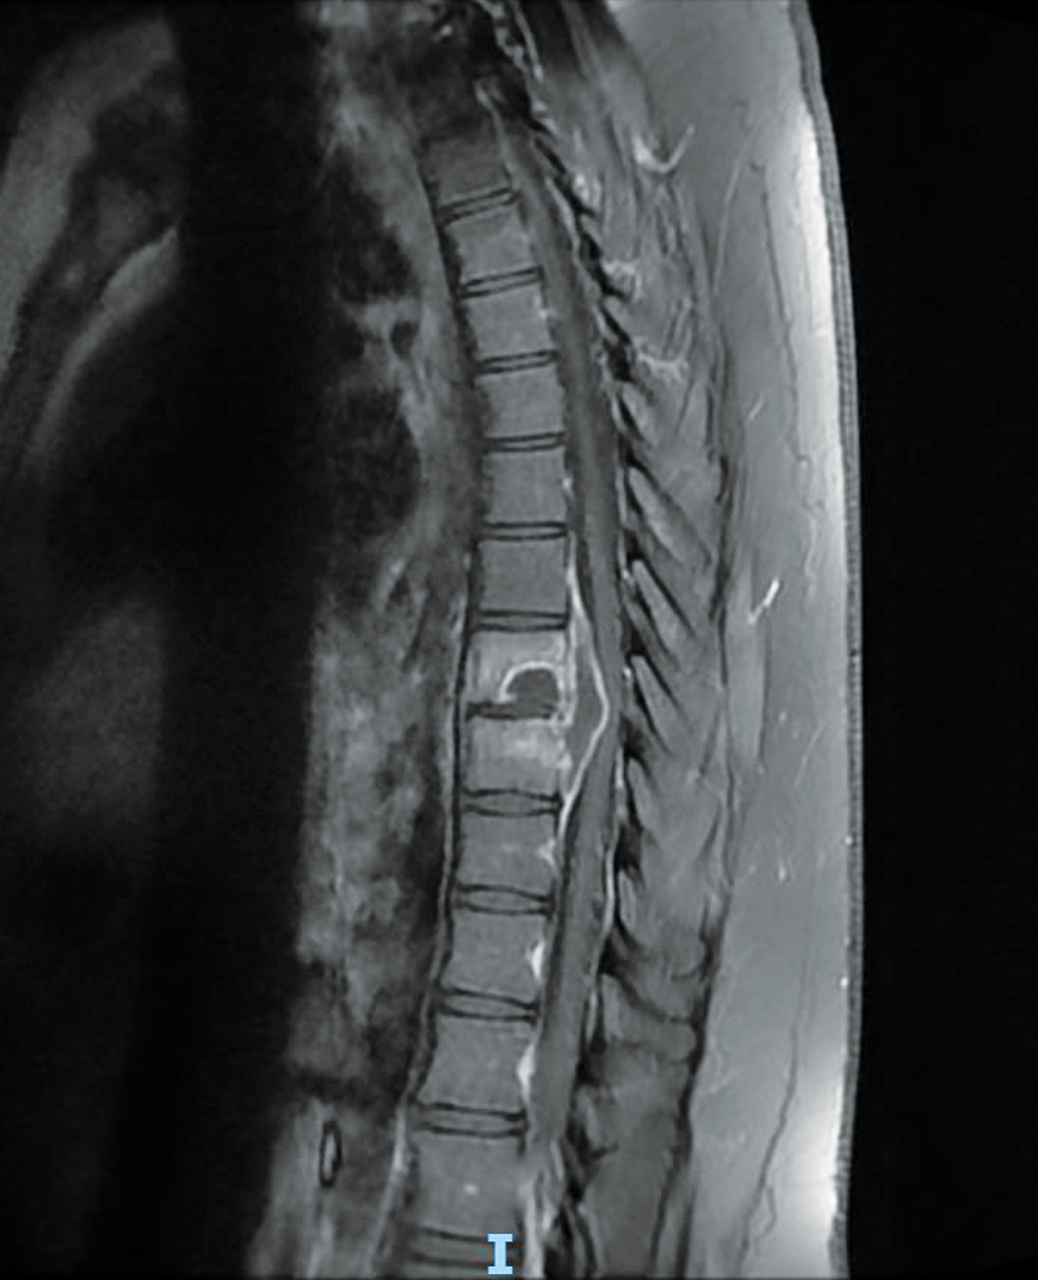

Un homme de 21 ans consulte pour une toux persistante évoluant depuis deux mois malgré deux lignes d’antibiothérapie. Il se plaint de rachialgies.

Le scanner thoracique met en évidence une pneumopathie abcédée. La recherche de BAAR (bacille acido-alcoolorésistant) est positive à l’examen direct. Le traitement antituberculeux est débuté. L’abcès épidural est drainé radiologiquement.